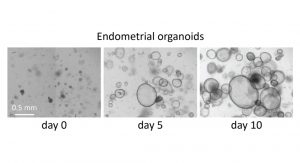

Building on this, we have continued to conduct experiments, such as those concerning the RNA transcriptome, and we hope that in the coming months we will be able to analyse the data from the whole genome sequencing that has been carried out. We were also able to establish an endometrial organoid model, which is proving to be very promising. This will give us better insights on the function of the rudiments.

In addition to the clinical element, we will also advance our fundamental research in the field of Mayer-Rokitansky-Küster-Hauser. As previously mentioned, we are eager to see the analysis of the genome data especially in combination with our transcriptome data. Our plan is to then move forward with possible candidate genes and interesting signalling pathways in endometrial organoids to better understand their impact on development and growth.